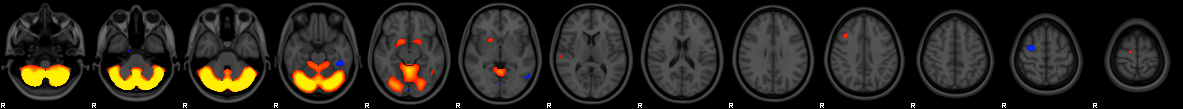

Component #4

Prior:

2% weight

Thickness

:

0% weight

Area

VBM

97% weight